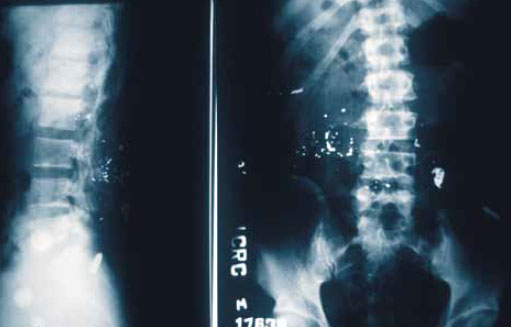

9. Металлические осколки: следует обратить внимание на разницу между неповрежденной пулей (M1) и разрушенной пулей (M2), как это показано на рисунке 6. Если сплошная металлическая оболочка пули разрушается и внутренний свинцовый сердечник разлетается в виде осколков, то это является показателем громадной нагрузки, приложенной к пуле, и большой передачи кинетической энергии на ткани (рисунок 7 и 8 3.35 и 10.5).

Рисунок 8. Тяжелый раздробленный перелом плечевой кости, образовавшийся после разрушения пули «свинцовый дождь»